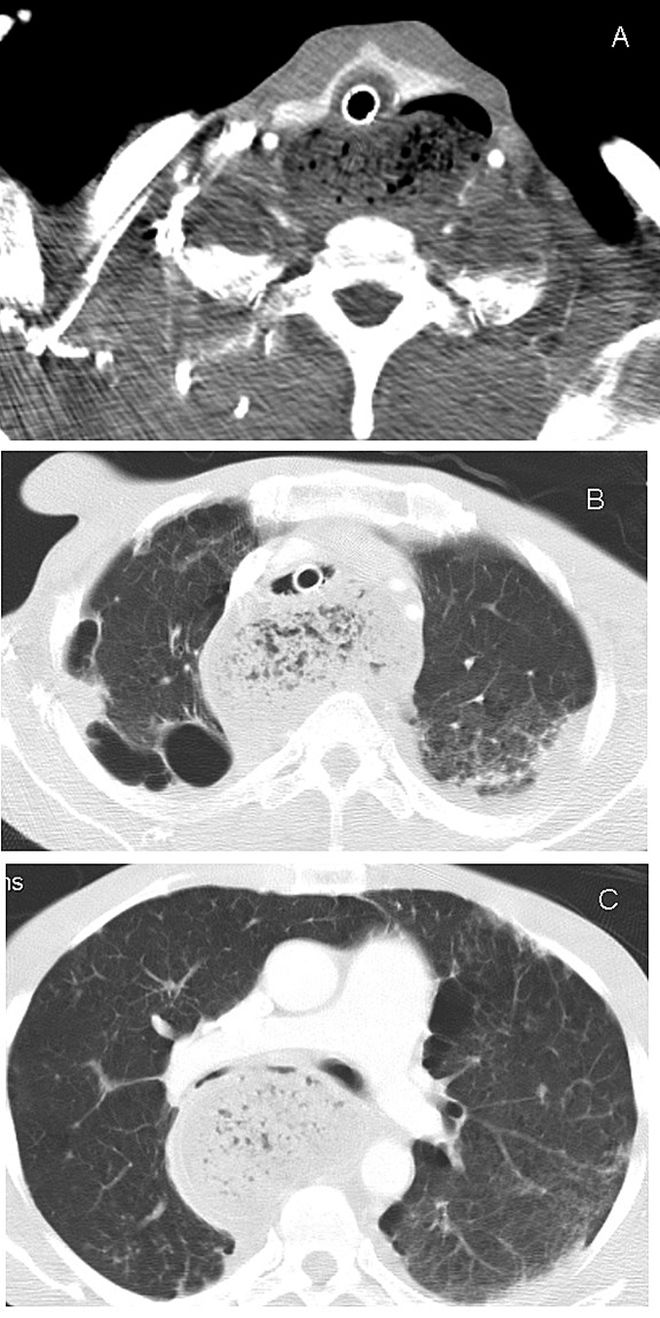

紧急支气管镜检查显示患者存在严重的气管及主支气管外源性压迫(图1),气管插管尖端以下水平的气道闭塞。将气管插管推进至气管受压区远端,气道压力及气体交换迅速恢复正常。数小时后,患者出现氧饱和度下降,原因被判定为右主支气管插管。

图1. 纤维支气管镜示(A)气管外源性压迫致管腔近乎完全闭塞,(B)双侧主支气管受压[2]

再次行支气管镜检查,并于颈部完全屈曲位将气管插管尖端精准定位于气管隆嵴正上方。胸部X线及CT影像显示纵隔增宽伴食管重度扩张,双侧主支气管受压(图2、图3)。

图2. 胸部X线. 胸部CT示食管重度扩张,导致喉部(A)、气管(B)及双侧主支气管(尤其右侧)(C)前向移位伴压迫[2]